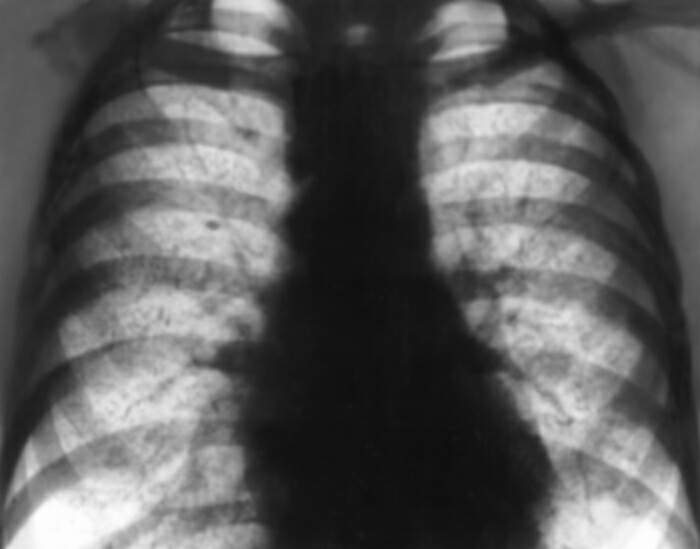

В начале болезни диагноз представляет определенные трудности. Исследование мокроты или рвотных масс обнаруживает наличие гемосидерофагов. Па рентгенограмме грудной клетки определяются небольшие инфильтраты или массивные поражения с вторичными ателектазами, эмфиземой и увеличением прикорневых лимфатических узлов. Достоверный прижизненный диагноз возможен только при открытой или пункционной биопсии легкого.